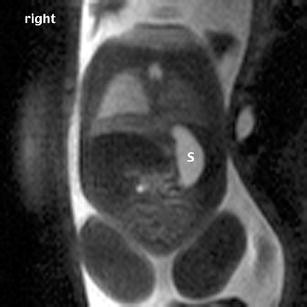

Different techniques are used in fetal cardiology, and their accuracy has been demonstrated on several occasions. Color Doppler US has proved to be a reliable and valuable tool in the diagnosis of fetal cardiac abnormalities. Magnetic resonance imaging (MRI) of the fetal heart has, so far, played no role in prenatal diagnostics. We report on a truncus arteriosus communis diagnosed prenatally during a screening ultrasound at 22 weeks of gestation. In addition to real-time ultrasound and color Doppler echocardiography, fetal MRI was performed. Fetal echocardiography arose suspicion of a type I common trunk. Fetal MR showed solely a widened vessel coursing retrocardially and additionally an inhomogeneous fluid distribution of the lung not shown on prenatal US. After termination of pregnancy at 23 weeks of gestation, MR fetography and autopsy were performed, and both found a type II common trunk. MR autopsy of the heart was very reliable in this case and could be an alternative when fetal pathology is not available for different reasons. Postmortem MRI was also able to demonstrate the inhomogeneous fluid distribution in the lung, which was confirmed by autopsy. Fetal and postmortem MR was reliable in the detection of an inhomogeneous fluid distribution in the lung not shown on prenatal US, providing a relevant additional finding to US. Therefore, MRI should be used more often in fetal cardiology, although it still must be further developed.

Fig. 1

Fig. 2

Fig. 3

Fig. 4

Fig. 5

Fig. 6

Fig. 7

Fig. 8